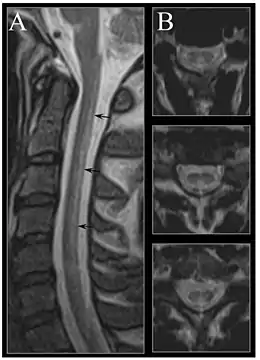

Severe vitamin B12 deficiency is associated with subacute combined degeneration of the spinal cord, which involves demyelination of the posterior and lateral columns of the spinal cord.[106] Symptoms include memory and cognitive impairment, sensory loss, motor disturbances, loss of posterior column functions and disturbances in proprioception.[107][108] In advanced stages of vitamin B12 deficiency, cases of psychosis, paranoia and severe depression have been observed, which may lead to permanent disability if left untreated.[106][107][108] Studies have shown the rapid reversal of the neurological symptoms of vitamin B12 deficiency, after treatment with high-dose of vitamin B12 supplementation; suggesting the importance of prompt treatment in reversing neurological manifestations.[109]

Early changes include a spongiform state of neural tissue, along with edema of fibers and deficiency of tissue. The myelin decays, along with axial fiber. In later phases, fibric sclerosis of nervous tissues occurs. Those changes occur in dorsal parts of the spinal cord and to pyramidal tracts in lateral cords and are called subacute combined degeneration of spinal cord.[144] Pathological changes can be noticed as well in the posterior roots of the cord and, to lesser extent, in peripheral nerves.

MRI of the brain may show periventricular white matter abnormalities. MRI of the spinal cord may show linear hyperintensity in the posterior portion of the cervical tract of the spinal cord, with selective involvement of the posterior columns.